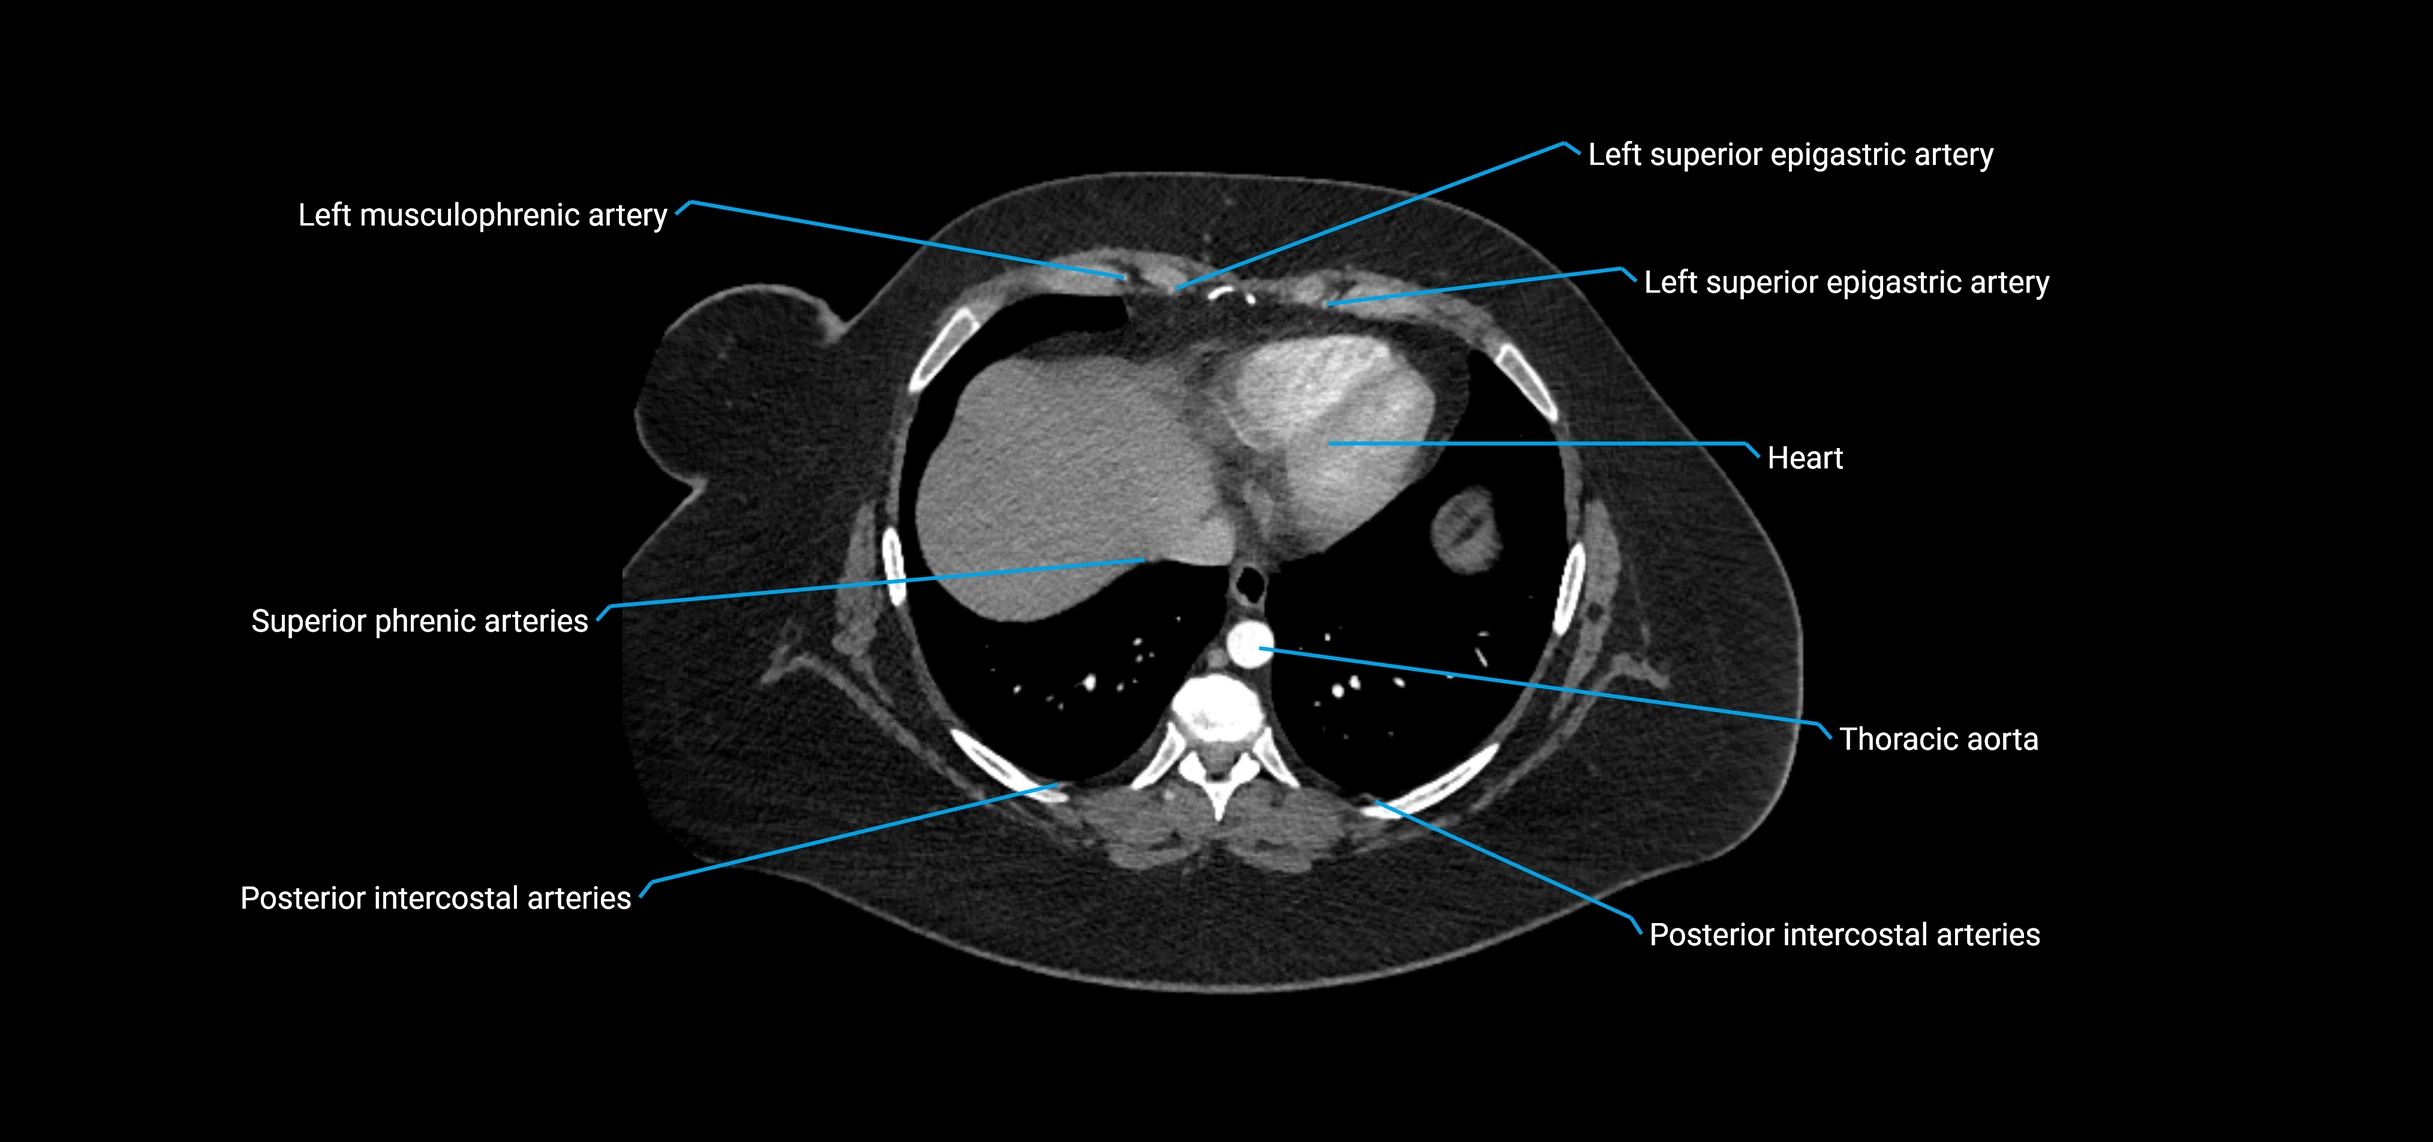

MRA (Magnetic Resonance Angiography):

• Contrast-enhanced MRA provides high-resolution imaging of the aorta and its branches

• Allows 3D reconstruction of visceral, parietal, and terminal branches

• Excellent for evaluating aneurysm size, dissection flap, stenosis, or preoperative planning

• Non-invasive alternative to conventional angiography